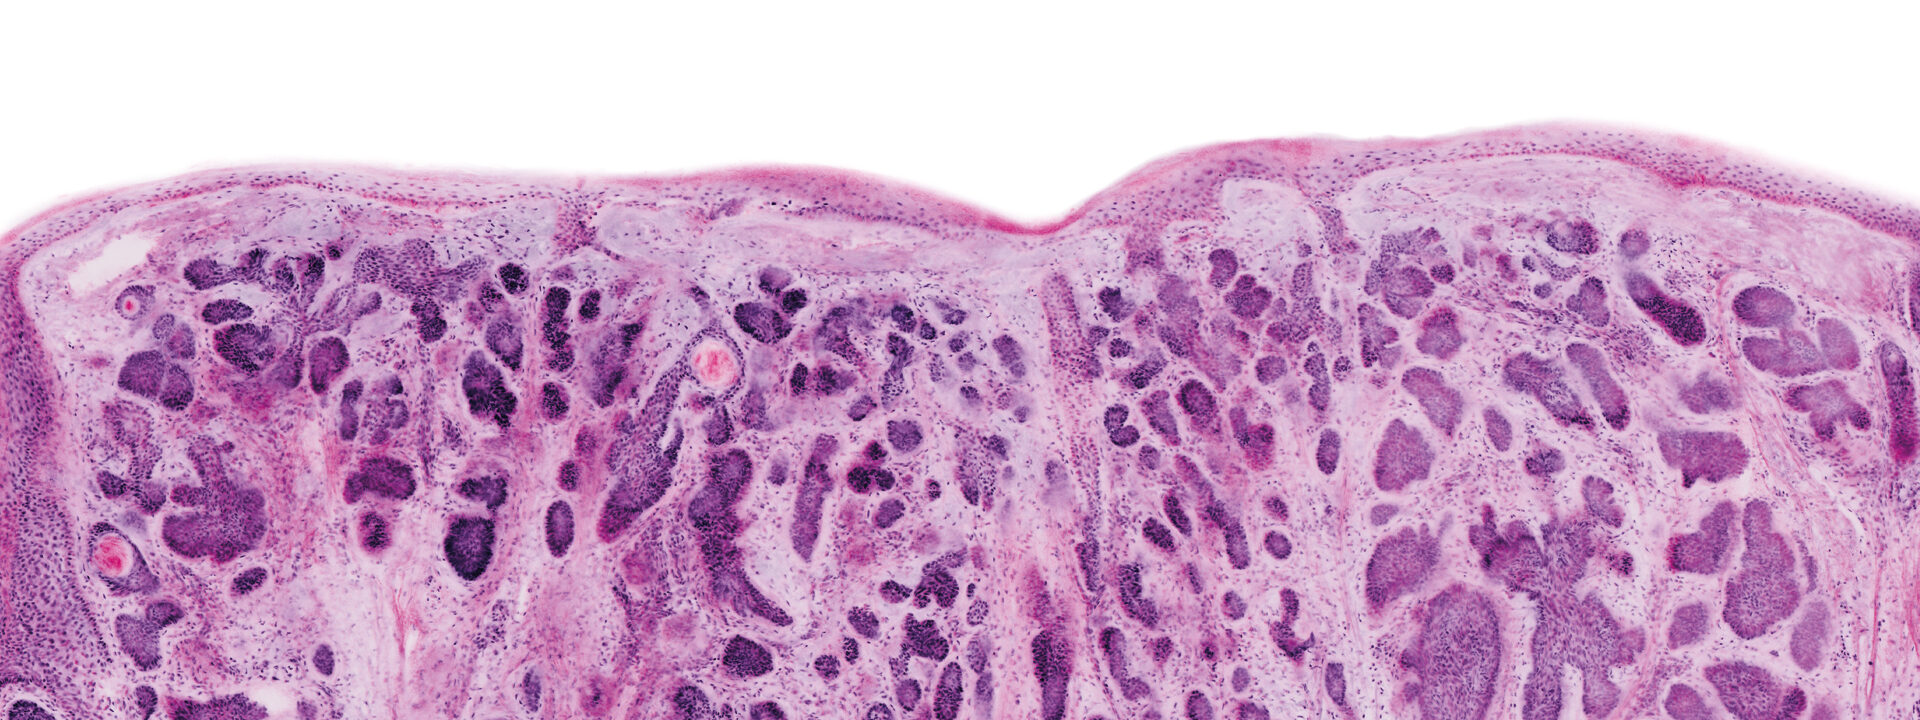

VivaScope Ex Vivo technology allows for direct pathological assesment during surgery. Like H&E staining, VivaScope images are generated from two components. Two lasers of different wavelengths create two distinct images, a fluorescence image and a reflectance image. Both signals are scanned simultaneously and are used to create pseudo-colored images. The device’s software uses an algorithm to translate the acquired image information into colors that resemble H&E.

Images courtesy of Dr Javiera Pérez-Anker. Basal cell carcinoma; imaged with the VivaScope 2500 (left) and after H&E staining (right).

The VivaScope technology is based on confocal microscopy (CLSM) and acquires images of superb optical resolution and contrast. The VivaScope 2500 images allow seamless zoom with up to 500x magnification and a great sample size.